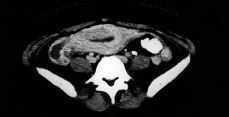

Figura 2. AngioRMN en la que se observa la trombosis de la vena ovárica derecha en su confluencia con la vena cava inferior.

A las 48 horas del primer TAC, e iniciado el tratamiento anticoagulante, la paciente presentó dolor en fosa lumbar derecha que irradia a FID, por lo que se practicó nuevo TAC y una angioRMN en los que se visualiza un discreto aumento en el volumen del trombo en VCI y en el componente de ectasia del uréter derecho, explicable por la relación anatómica entre éste y la vena ovárica trombosada. Se aumentan las dosis de heparina sódica a 26.000 UI/24h y se modifica la pauta antibiótica: cefotaxima, clindamicina y doxiciclina, remitiendo el cuadro álgico y febril a los cuatro días del inicio de este tratamiento.